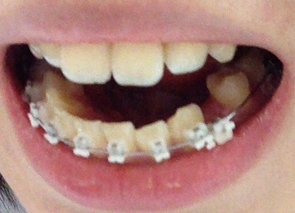

상악은 제가 아직 장치를 달지 않은 상태이기 때문에 다음 월치료때까지는 다시 한번 상악에 있는 치아 발치를 해야하는 상황인데

이번에 가니 상악 치아들중 발치해야 하는 부분을 알려주셨답니다. 그부분은 사진에보이는 뿌리만 남아있는 한곳과 대칭다는 반대편쪽 하나 각각 5번,5번 인 치아들이 었어요.,

드디어 다음 월치료때는 상악에도 장치를 부착하시는군요!